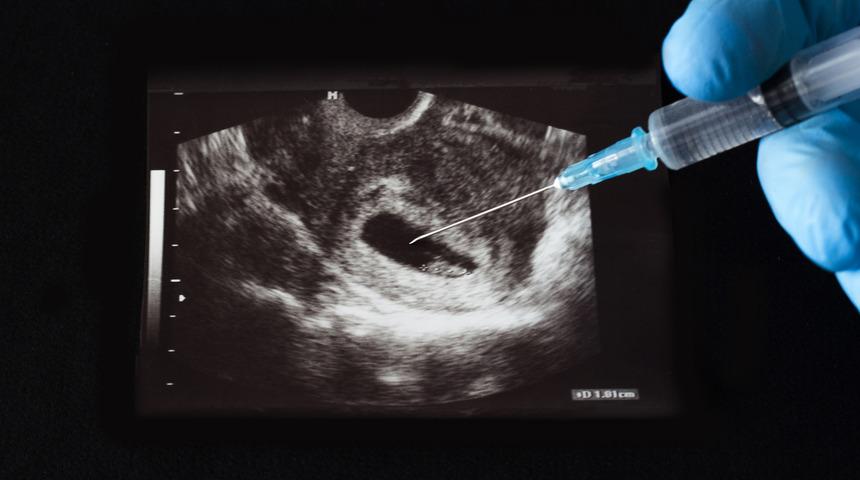

Arjantin'de, kürtajın tecavüz vakası ya da anne hayatının tehlikede olmasıyla sınırlandırılmasını kaldırmaya yönelik tasarı Meclis'in ardından Senato'dan da geçti.

Yasa, hamileliğin 14. haftasına kadar kürtaj yapılmasına olanak tanıyor.

Arjantin'de mevcut yasalar çerçevesinde kürtaj yaptıran kadınlar cezalandırılıyor. Sadece tecavüz sonucu olması veya annenin sağlığını tehlikeye atması durumunda gebeliğin sonlandırılmasına izin veriliyor.